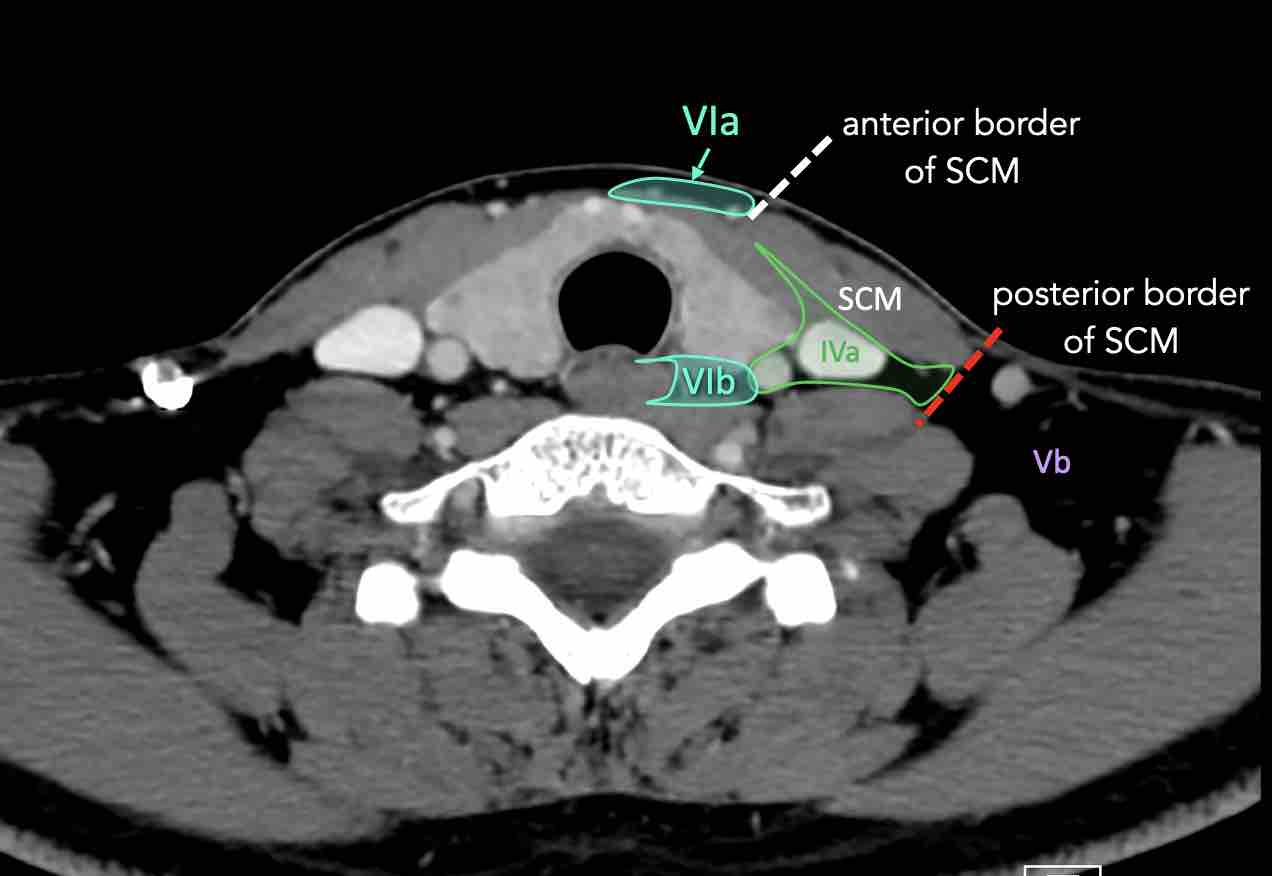

IV – Tĩnh mạch cảnh dưới và hố thượng đòn trong

Ranh giới giữa tầng IVa và IVb được xác định tùy ý tại vị trí 2 cm phía trên khớp ức đòn.

V – Tam giác cổ sau và hố thượng đòn

Tầng V chứa các hạch của nhóm tam giác cổ sau nằm ở phía sau cơ ức đòn chũm, xung quanh phần dưới của thần kinh phụ gai sống và các mạch máu cổ ngang.

VI – Cổ trước

Tầng này chứa các hạch tĩnh mạch cảnh trước nông (tầng VIa) và các hạch sâu hơn bao gồm hạch trước thanh quản, trước khí quản, cạnh khí quản và hạch thần kinh thanh quản quặt ngược (tầng VIb).